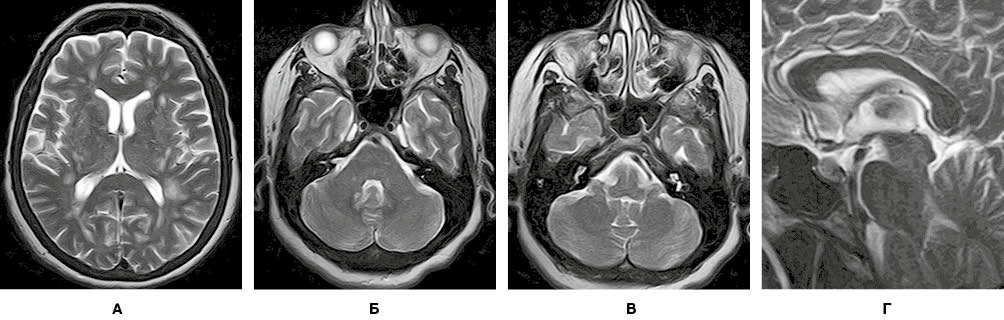

На рисунку 1 представлено МРТ-зображення головного мозку пацієнта з ГРЕМ у режимах Т2, Т2/Flair та Т1 із внутрішньовенним контрастуванням. Зокрема, візуалізуються двобічні вогнища округлої та овоїдної форми, гіперінтенсивні в режимах Т2 та Т2/Flair, які в більшості випадків накопичують контраст.

На рисунку 4 наведено МРТ-зображення головного мозку пацієнта з гострим геморагічним лейкоенцефалітом (хворобою Херста) у режимі Т2*/T2 GRE, де візуалізуються двобічні гіперінтенсивні вогнища, два з яких містять геморагічний компонент, та в режимі Т2. А на рисунку 5 — МРТ-зображення головного мозку пацієнта з ГРЕМ у режимі Т2 — продемонстровано важливу ознаку ГРЕМ (на відміну від РС): відносну інтактність мозолистого тіла, стовбура мозку, середніх мозочкових ніжок та мозочка, які в разі РС, як правило, уражаються першочергово. Вказана ознака не завжди є показовою, але має високу інформативність для диференційної діагностики.

Завдяки виконаному МРТ-дослідженню головного мозку візуалізувано множинні вогнища, переважно овоїдної та округлої форм, розташовані в глибокій білій речовині обох семіовальних центрів. Вогнища гіперінтенсивні в режимах Т2/Flair і Т2, поліморфні. Типовою клінічною ознакою, характерною для перебігу ГРЕМ, на відміну від РС, є те, що більшість запальних вогнищ накопичують контраст. На зображеннях у режимі Т2 GRE не виявлено даних, які б могли свідчити про крововиливи в структурі вогнищ. МРТ-зображення головного мозку пацієнта в різних режимах, представлені на рисунках 6-9, підтверджують діагноз ГРЕМ.